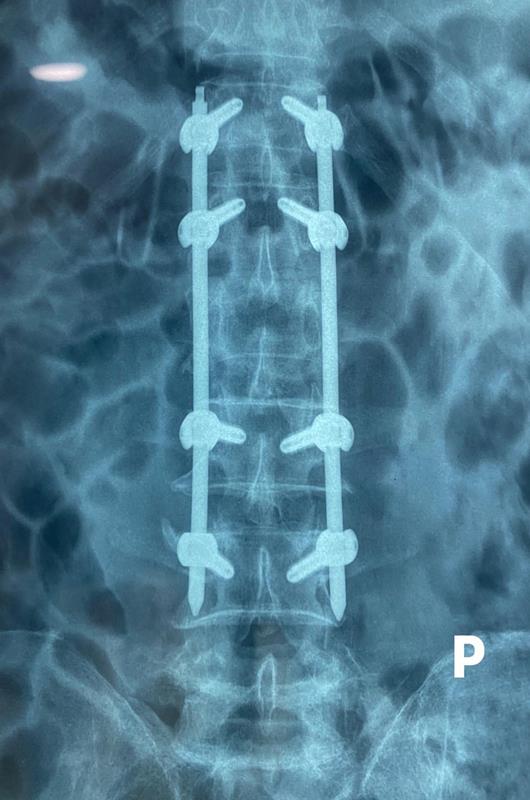

ThS-BS Trần Đức Duy Trí, Khoa Chấn thương chỉnh hình, Bệnh viện Hoàn Mỹ ITO Đồng Nai cho biết, để điều trị cho bệnh nhân, các bác sĩ đã áp dụng phương pháp phẫu thuật ít xâm lấn tối thiểu. Bệnh nhân được chỉ định bắt vít qua da từ đốt N12 đến L4 và giải ép gián tiếp bằng kỹ thuật nắn chỉnh trục dây chằng (Ligamentoaxis). Kết quả chụp X-Quang sau mổ cho thấy chiều cao thân sống L2 được phục hồi, còn phim chụp CT cho thấy kích thước ống sống rộng lại gần bình thường. Sau mổ, bệnh nhân giảm đau lưng, hai chân vận động tốt. Sau hơn 1 ngày, bệnh nhân có thể đi lại bằng nạng và tiểu tiện bình thường. Đến nay, bệnh nhân đã được xuất viện.

Hình ảnh phim chụp cột sống bệnh nhân sau khi được phẫu thuật